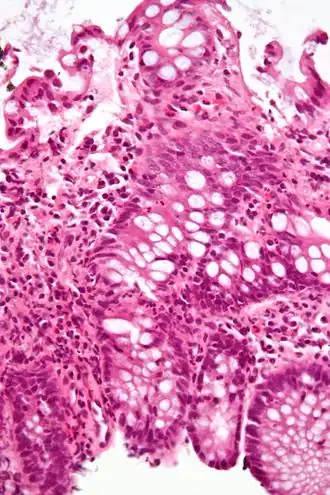

Une colite est une inflammation du côlon.